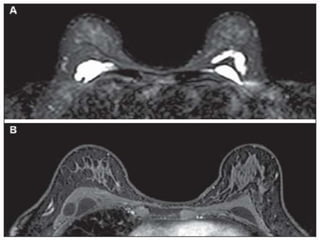

Além da mamografia existem ainda outros meios de

diagnóstico de câncer de mama além da mamografia, tais

como ressonância magnética, ultrassonografia e

tomossíntese.

RESSONÂNCIA MAGNÉTICA

ULTRASSONOGRAFIA

TOMOSSÍNTESE